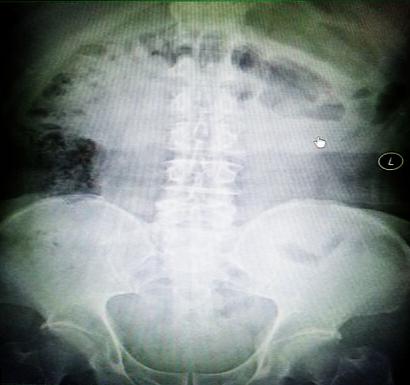

受試患者在結腸端端吻合術中,使用我司新研制產(chǎn)品達到了理想的預期效果?;颊咝g后7天、14天X光片顯影,可降解腸道支架均能按研制設計的預期時間節(jié)點保持應有強度,術后21天X光片顯示可降解腸道支架已完全破碎,并排出體外。在整個試驗過程中,病患無任何不良反映,耐受良好。